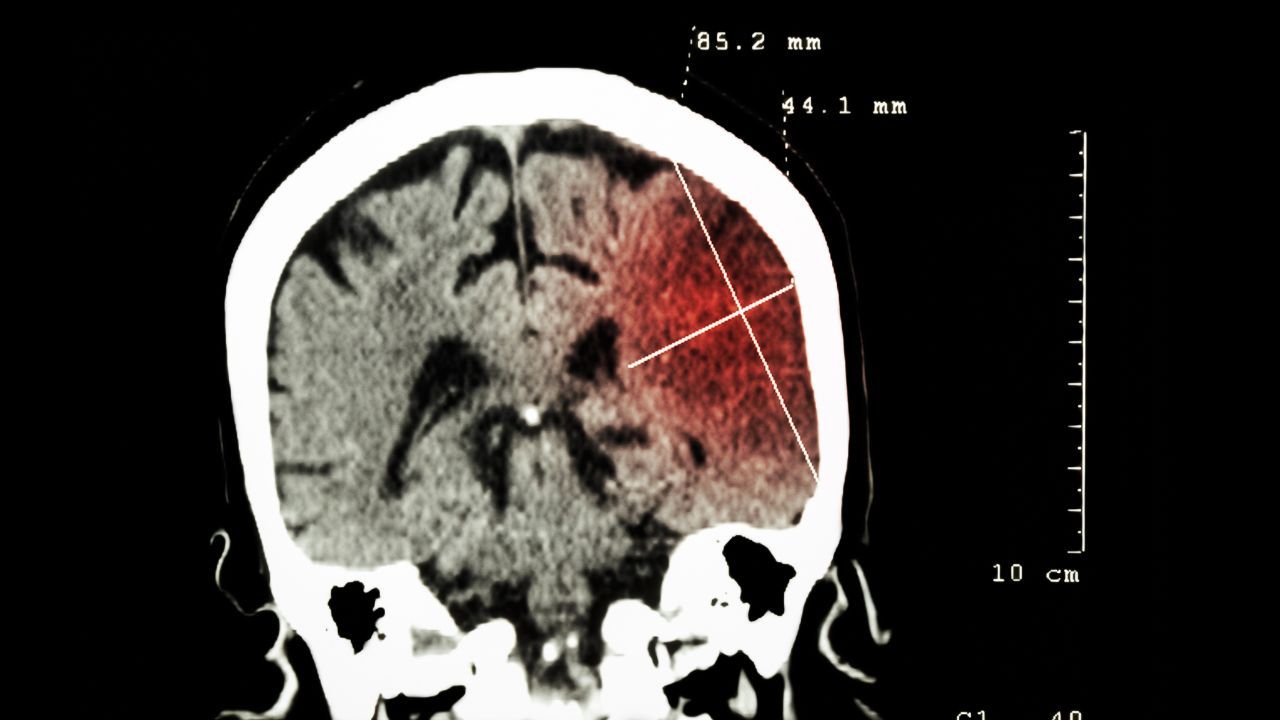

Wysyp udarów przed 50 r.ż. Jakie są przyczyny?

Jeszcze niedawno udar kojarzył się głównie z wiekiem emerytalnym. Dziś neurologiczne „zawały” coraz częściej wywracają życie ludzi po trzydziestce – a każda minuta zwłoki w reakcji kosztuje bezcenne neurony. Sprawdź, co kryje się za tą zmianą i jak rozpoznać pierwsze sygnały.

Udar nie jest chorobą starych ludzi

Ryzyko udaru rzeczywiście rośnie z wiekiem, ale udary „nie wybierają”: w amerykańskich statystykach aż 38 proc. pacjentów hospitalizowanych z tego powodu miało mniej niż 65 lat. Coraz młodsi pacjenci pojawiają się na oddziałach ratunkowych z objawami udaru. Skąd wynika ten niebezpieczny trend? Wg polskich danych, liczba udarów przekracza 90 tys. rocznie, a „niepokojący przyrost dotyczy młodych dorosłych” – przede wszystkim tych żyjących w ciągłym stresie i zaniedbujących profilaktykę.